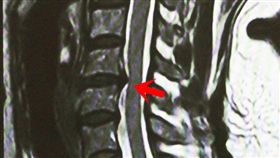

肩頸痠痛轉脖子 美髮師竟椎間盤突出

51歲孫小姐是美髮師,因長時間舉手、彎脖,經常肩頸痠...

女師滑倒腰椎椎間盤爆裂 大小便失禁

一名35歲女教師,某天於家中下樓梯時不慎滑倒,屁股跌...

以為閃到腰!男尿變少下背劇痛險癱瘓

出現腰酸背痛的症狀,千萬別以為只是「閃到腰」!台中3...

他背痛難忍!醫嚇:椎間盤被細菌吃掉

一名54歲陳姓男病患感到後腰疼痛,曾經罹患過骨刺,自...